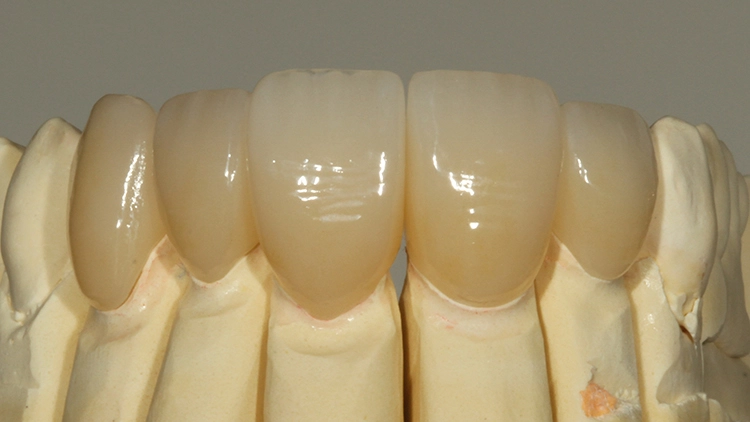

Bei der jetzt anstehenden Teilkronen- bzw. Veneerversorgung der Zähne 12 bis 23 blieb zunächst die Frage des keramischen Restaurationsmaterials zu klären. Neben der bewährten und hochästhetischen glasbasierten Keramik [2,8,10,14–16] eignen sich heutzutage transluzente Zirkonoxidmaterialien hervorragend für die ästhetische Ausgestaltung von Frontzahnbereichen [11], da sie genauso gut verklebt werden können wie Glaskeramiken [9,23].

Gerade im Bereich parafunktional gefährdeter Areale punktet das gegenüber der klassischen Glaskeramik doch deutlich bruchfestere Vollzirkonmaterial. Da bei der Patientin bereits mehrfach Füllungen und Inzisalkanten frakturierten, fiel in diesem Fall die Materialauswahl auf ein hochtransluzentes, polychromes Vollzirkon (zolid fx multilayer, Amann Girrbach), welches mit Ceramotion ZR (Dentaurum) verblendet wurde. Hergestellt wurde die Arbeit (Abb. 10 und 11) im eigenen Meisterlabor durch ZTM Richard Bohrer.